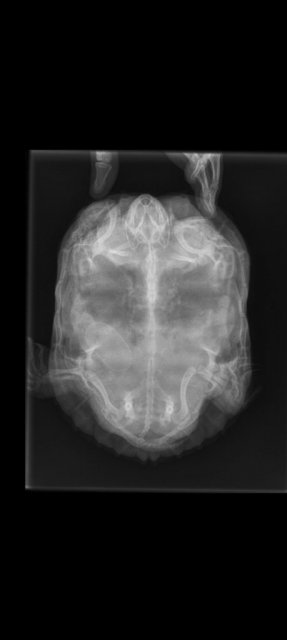

Screenshot_2024-02-18-16-33-34-15_68e74cc0265513bba3f4cf8e2c9891fe.jpg

@moth И снова здравствуйте. Прошел месяц, черепах не снеслась. Свозили на рентген, теперь яйца три. Нет риска, что они внутри неё могут лопнуть?